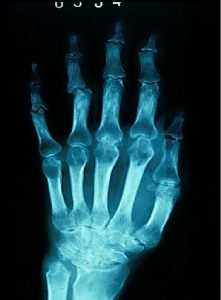

术前(左)和术后(右)关节X光图片病人三年来第一次外出手术